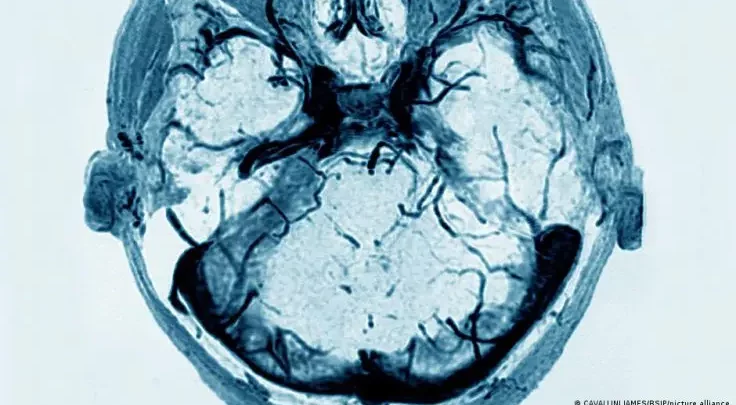

كيف تبدو أمخاخ من يعانون من مرض السكري؟

وشملت الدراسة، التي نشرها معهد كارولينسكا على موقعه الإلكتروني، أكثر من 31 ألف شخص تتراوح أعمارهم بين أربعين وسبعين عاماً تم إخضاعهم للفحص بالرنين المغناطيسي للمخ.